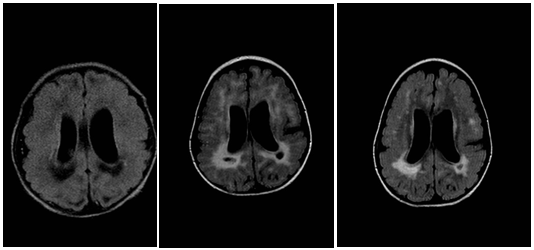

Figure 2: A: age 7 days; B: age 12 months; C: age 2,5 years

Brain MRI (1,5 Tesla). Axial T2 Flair sequences at the same level through the lateral ventricles: periventricular leukoencephalopathy with periventricular pseudocysts next to trigonum of the lateral ventricles-evolution over the time.

Congenital cytomegalovirus infection was confirmed by specific serology and cytomegalovirus DNA polymerase chain reaction in blood and urine sample taken on the fifth day. In the mother’s blood were detected CMV-IgG antibodies of high avidity. The girl received intravenous treatment with gancyclovir during the 3-week period, subsequent with valgancyclovir liquid next three weeks. Control blood CMV-DNA PCR was negative, but five months later repeated viremia with 190 DNA copies/ ml, and viruria with 576 002 DNA copies/ml, was detected. She received one more, 6-week cycle of valgancyclovir therapy. Afterwards, repeated blood polymerase chain reaction tests were continuously negative. From the beginning the clinical course showed delayed motor milestones, she had sensorineural deafness on the left side and poor social contact, she was unable to sit without support until the age of 2.5 years. There were no seizures and the EEG was normal. Chorioretinitis wasn’t found. From early infancy she underwent continuous multidisciplinary habilitation including physical, visual, speech and language therapy. Neurodevelopmental outcome at the age of 3 years showed severe neuromotor dysfunction, predictive of bilateral spastic palsy and severe mental impairment, absent language development, marked microcephaly, but no epilepsy so far. We evaluated hearing status using brainstem-evoked reponses after ganciklovir therapy in the neonatal period. She maintained normal hearing on the right side, but severe sensoneuronal hearing loss on the left side remained. At the age of 1year, control brain MRI (1.5 Tesla) was performed and showed reduced volume of periventricular white matter, still mildly dilated lateral ventricles, more developed corpus callosum, patchy periventricular gliosis occipitally with pseudocystic changes (Figure 2B) and bilateral frontal and temporal pachygyria (Figure 1B). Additional brain MRI (1.5 Tesla) was performed at the age of 2,5 years and revealed only mildly dilated occipital, and temporal horns, normal corpus callosum, minimal occipital and left temporal periventricular gliosis, less prominent pseudocystic changes (Figure 2C, Figure 3C), frontal and temporal bilateral pachygyria (Figure 1C). MRI at the age of 2.5 years showed unchanged periventricular calcifications (like on the Figure 1A).